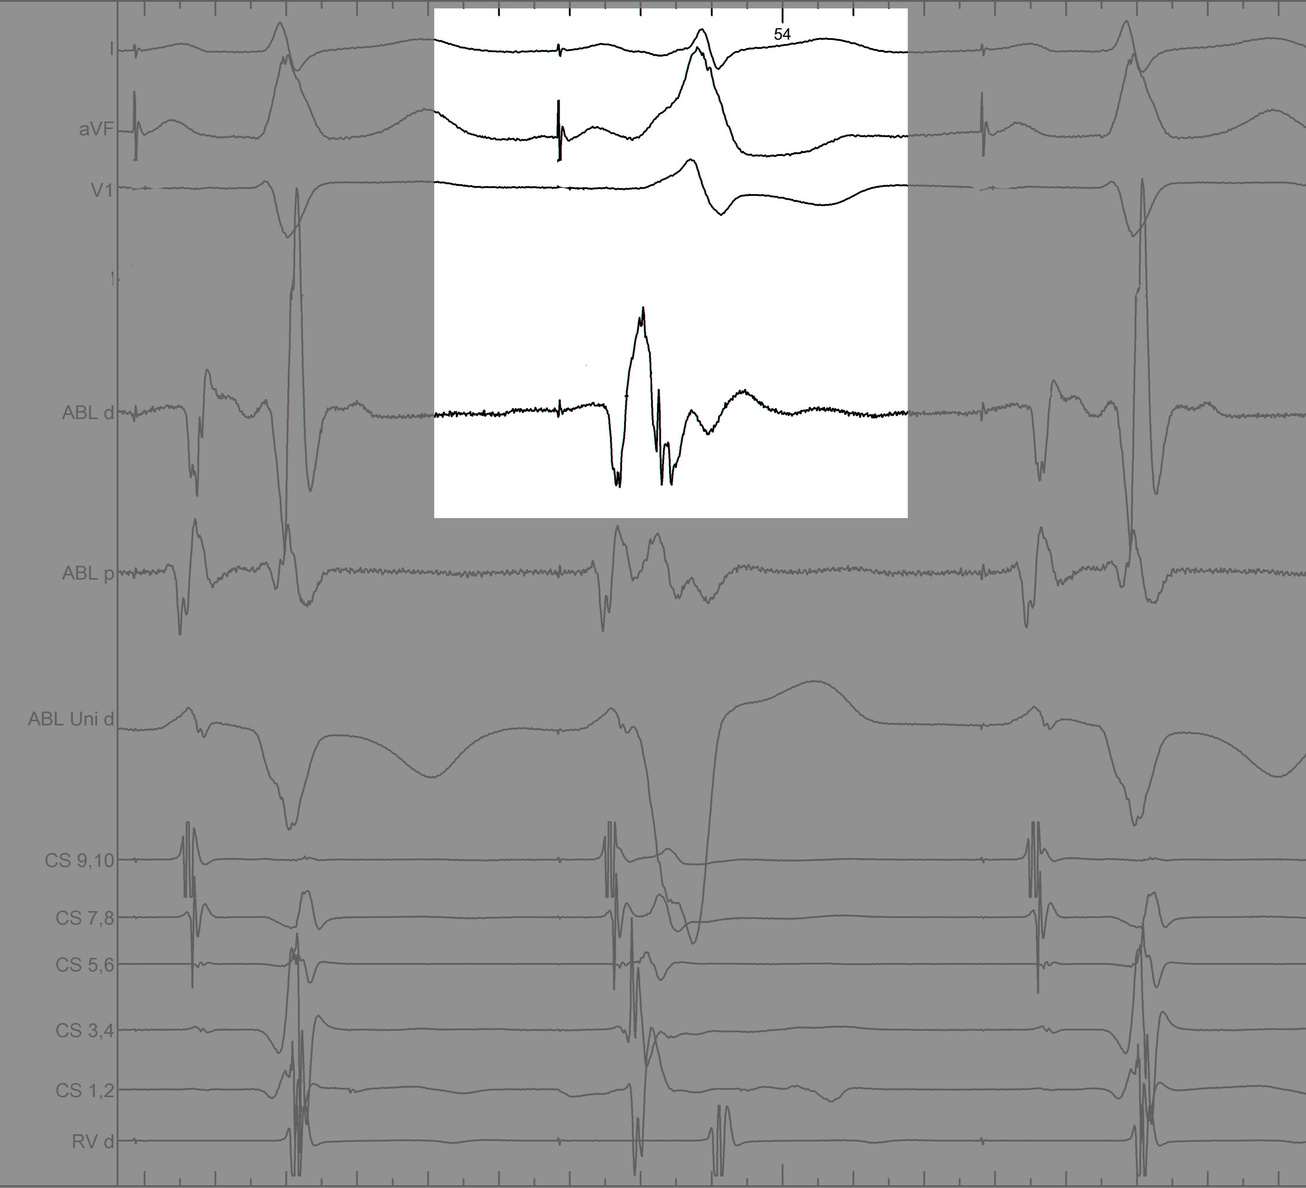

signals.jpg

Mapping in diverticulum - CSE potential most important

div_schematic.jpg

Selvaraj RJ et al. Radiofrequency ablation of posteroseptal accessory pathways associated with coronary sinus diverticula. J Interv Card Electrophysiol. 2016 Nov;47(2):253-259. doi: 10.1007/s10840-016-0113-x.